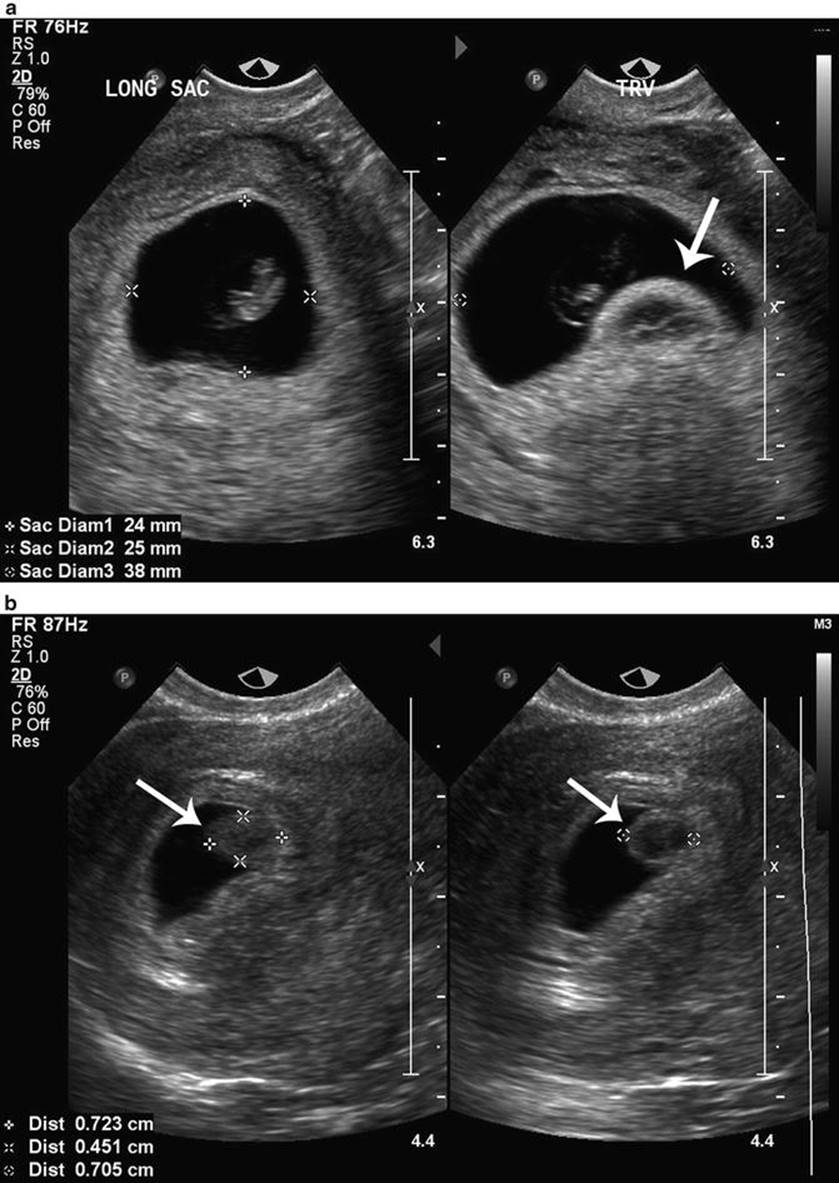

The gestational sac forms early in pregnancy to enclose an embryo and amniotic fluid. Certain sac characteristics can indicate a compromised pregnancy.

Predicting pregnancy failure in 'empty' gestational sacs - Nyberg - 2003 - Ultrasound in Obstetrics & Gynecology - Wiley Online Library

Defining safe criteria to diagnose miscarriage: prospective observational multicentre study

First-Trimester Ultrasound: Early Pregnancy Failure - First-Trimester Ultrasound: A Comprehensive Guide

Early Pregnancy Loss (Embryonic Demise) Imaging: Practice Essentials, Ultrasonography